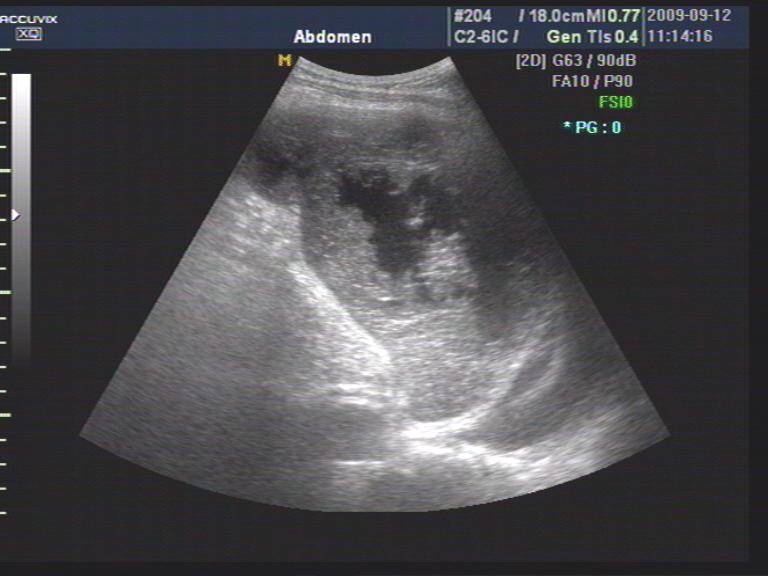

脾破裂彩超

脾破裂彩超,

脾破裂图像收集

创伤性脾破裂

腹部超声 创伤性脾破裂的超声诊断-大为b超彩超机厂家